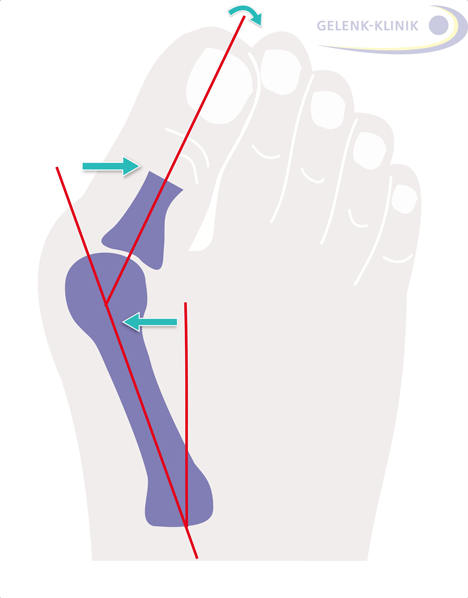

Schmerzen am Fußballen: Hallux valgus an der Großzehe

Der Hallux valgus ist eine weit verbreitete Fehlstellung, bei der die Großzehe nach außen abweicht. © Gelenk-Klinik

Der Hallux valgus (Ballenzeh) ist die Folge eines Spreizfußes. Die abgespreizte Großzehe kann zu schmerzhafter Arthrose im Großzehengrundgelenk führen (Hallux rigidus). Häufig entzünden sich die Schleimbeutel im Bereich des Fußballens und schwellen schmerzhaft an (Bursitis). Dadurch verstärkt sich die bei Hallux valgus vorhandene Exostose noch und es entstehen – vor allem bei ungeeignetem Schuhwerk – starke Schmerzen. Weitere Auffälligkeiten, die aus Vorfußerkrankungen resultieren, sind Hammerzehen und Krallenzehen. Dies sind Fehlstellungen der Kleinzehen, die durch Schiefstellung der Großzehe und Überlastung der Kleinzehen begünstigt werden.